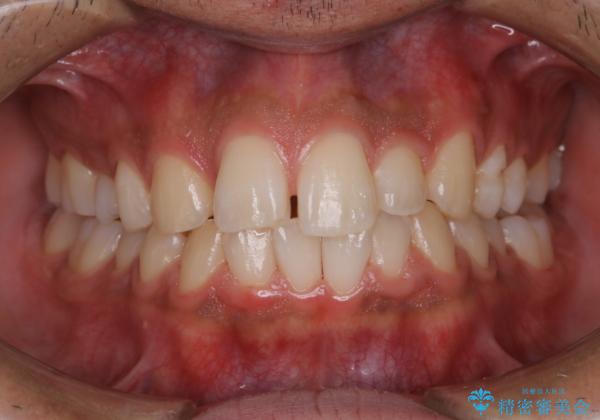

矯正をスタートする前にクリーニングを行いました。PMTC60分コースを行いました。

10年ぶりのクリーニングのため着色や歯石、プラークの量は多めでした。